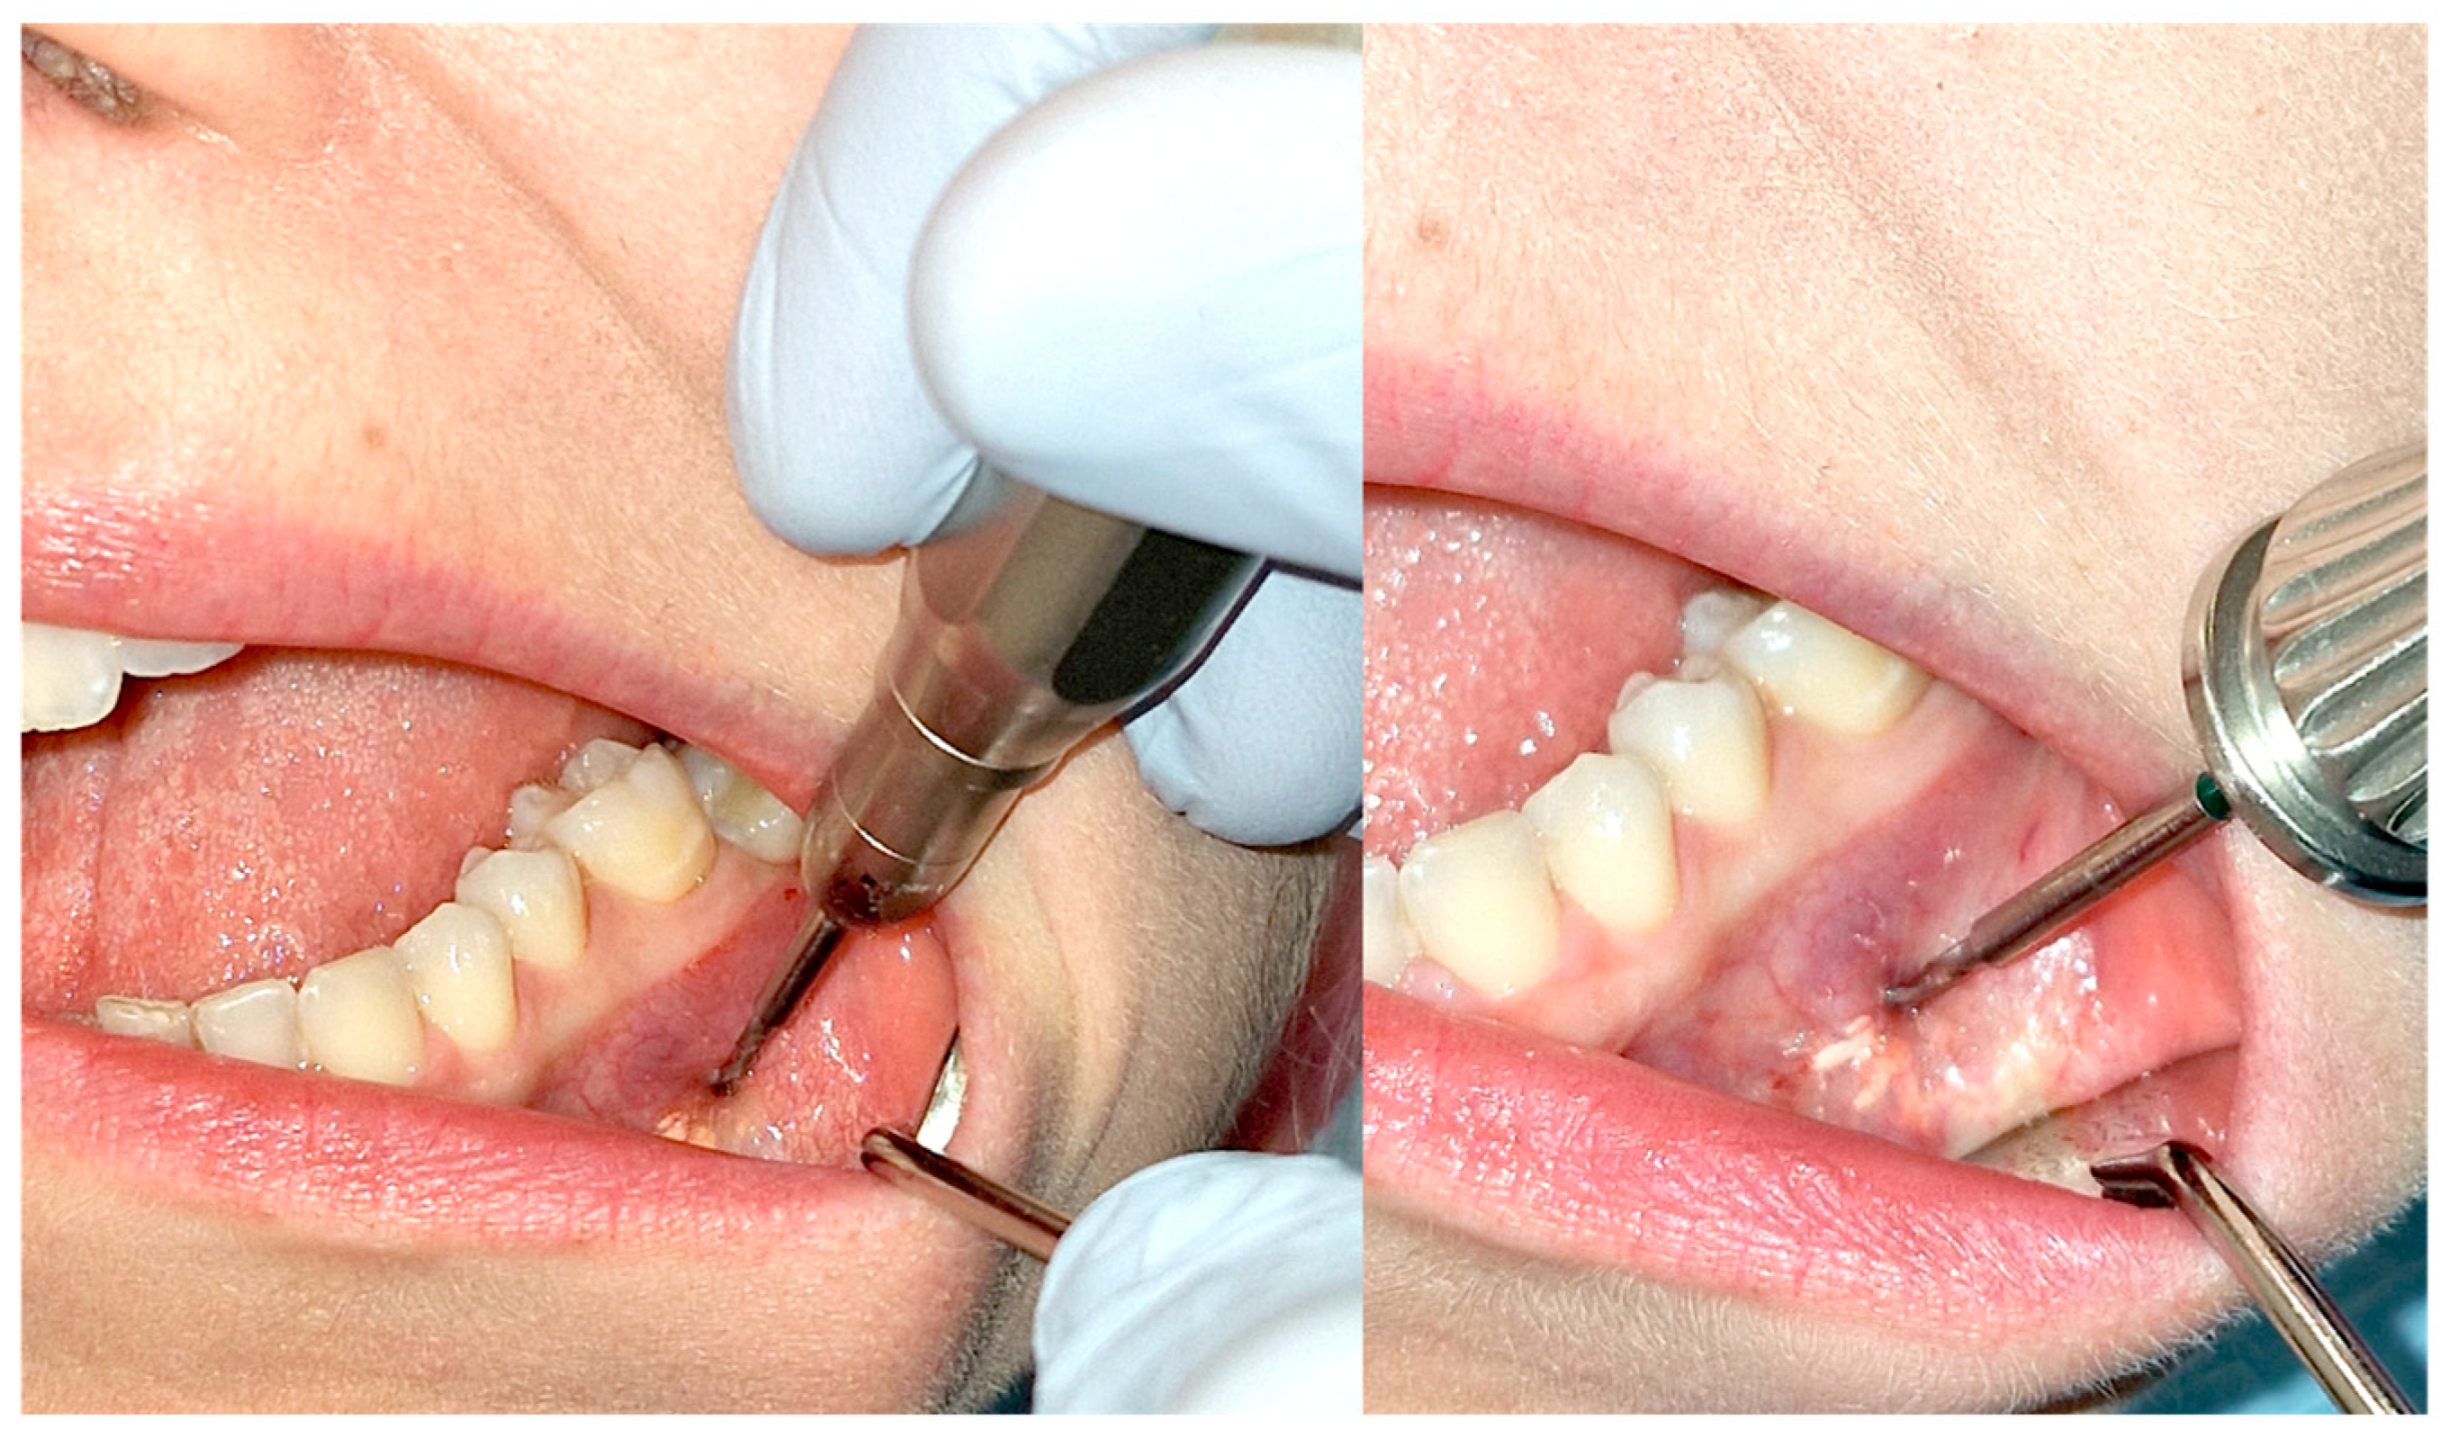

3.2. Injections